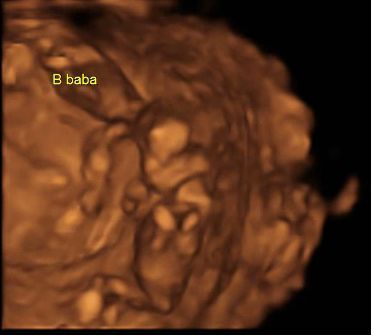

Szandra: Akkor szigorúan tartsd be amit mondanak. Vigyáz a babádra nagyon!!! És a kórházban mit csináltak veled? Infúziót kaptál? Vagy csak megvizsgáltak? ÉS eddig nem látták, hogy lehet hogy két baba van?